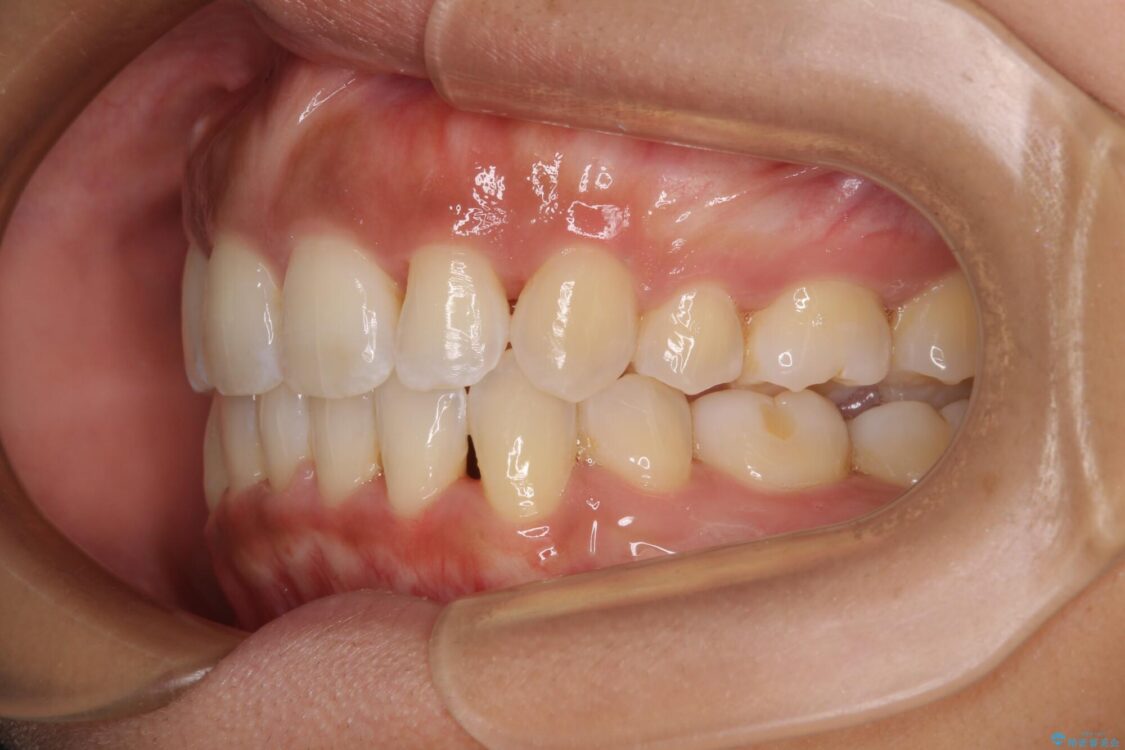

治療前

• 抜歯矯正で唇を閉じやすく 目立たないワイヤー装置 治療前画像